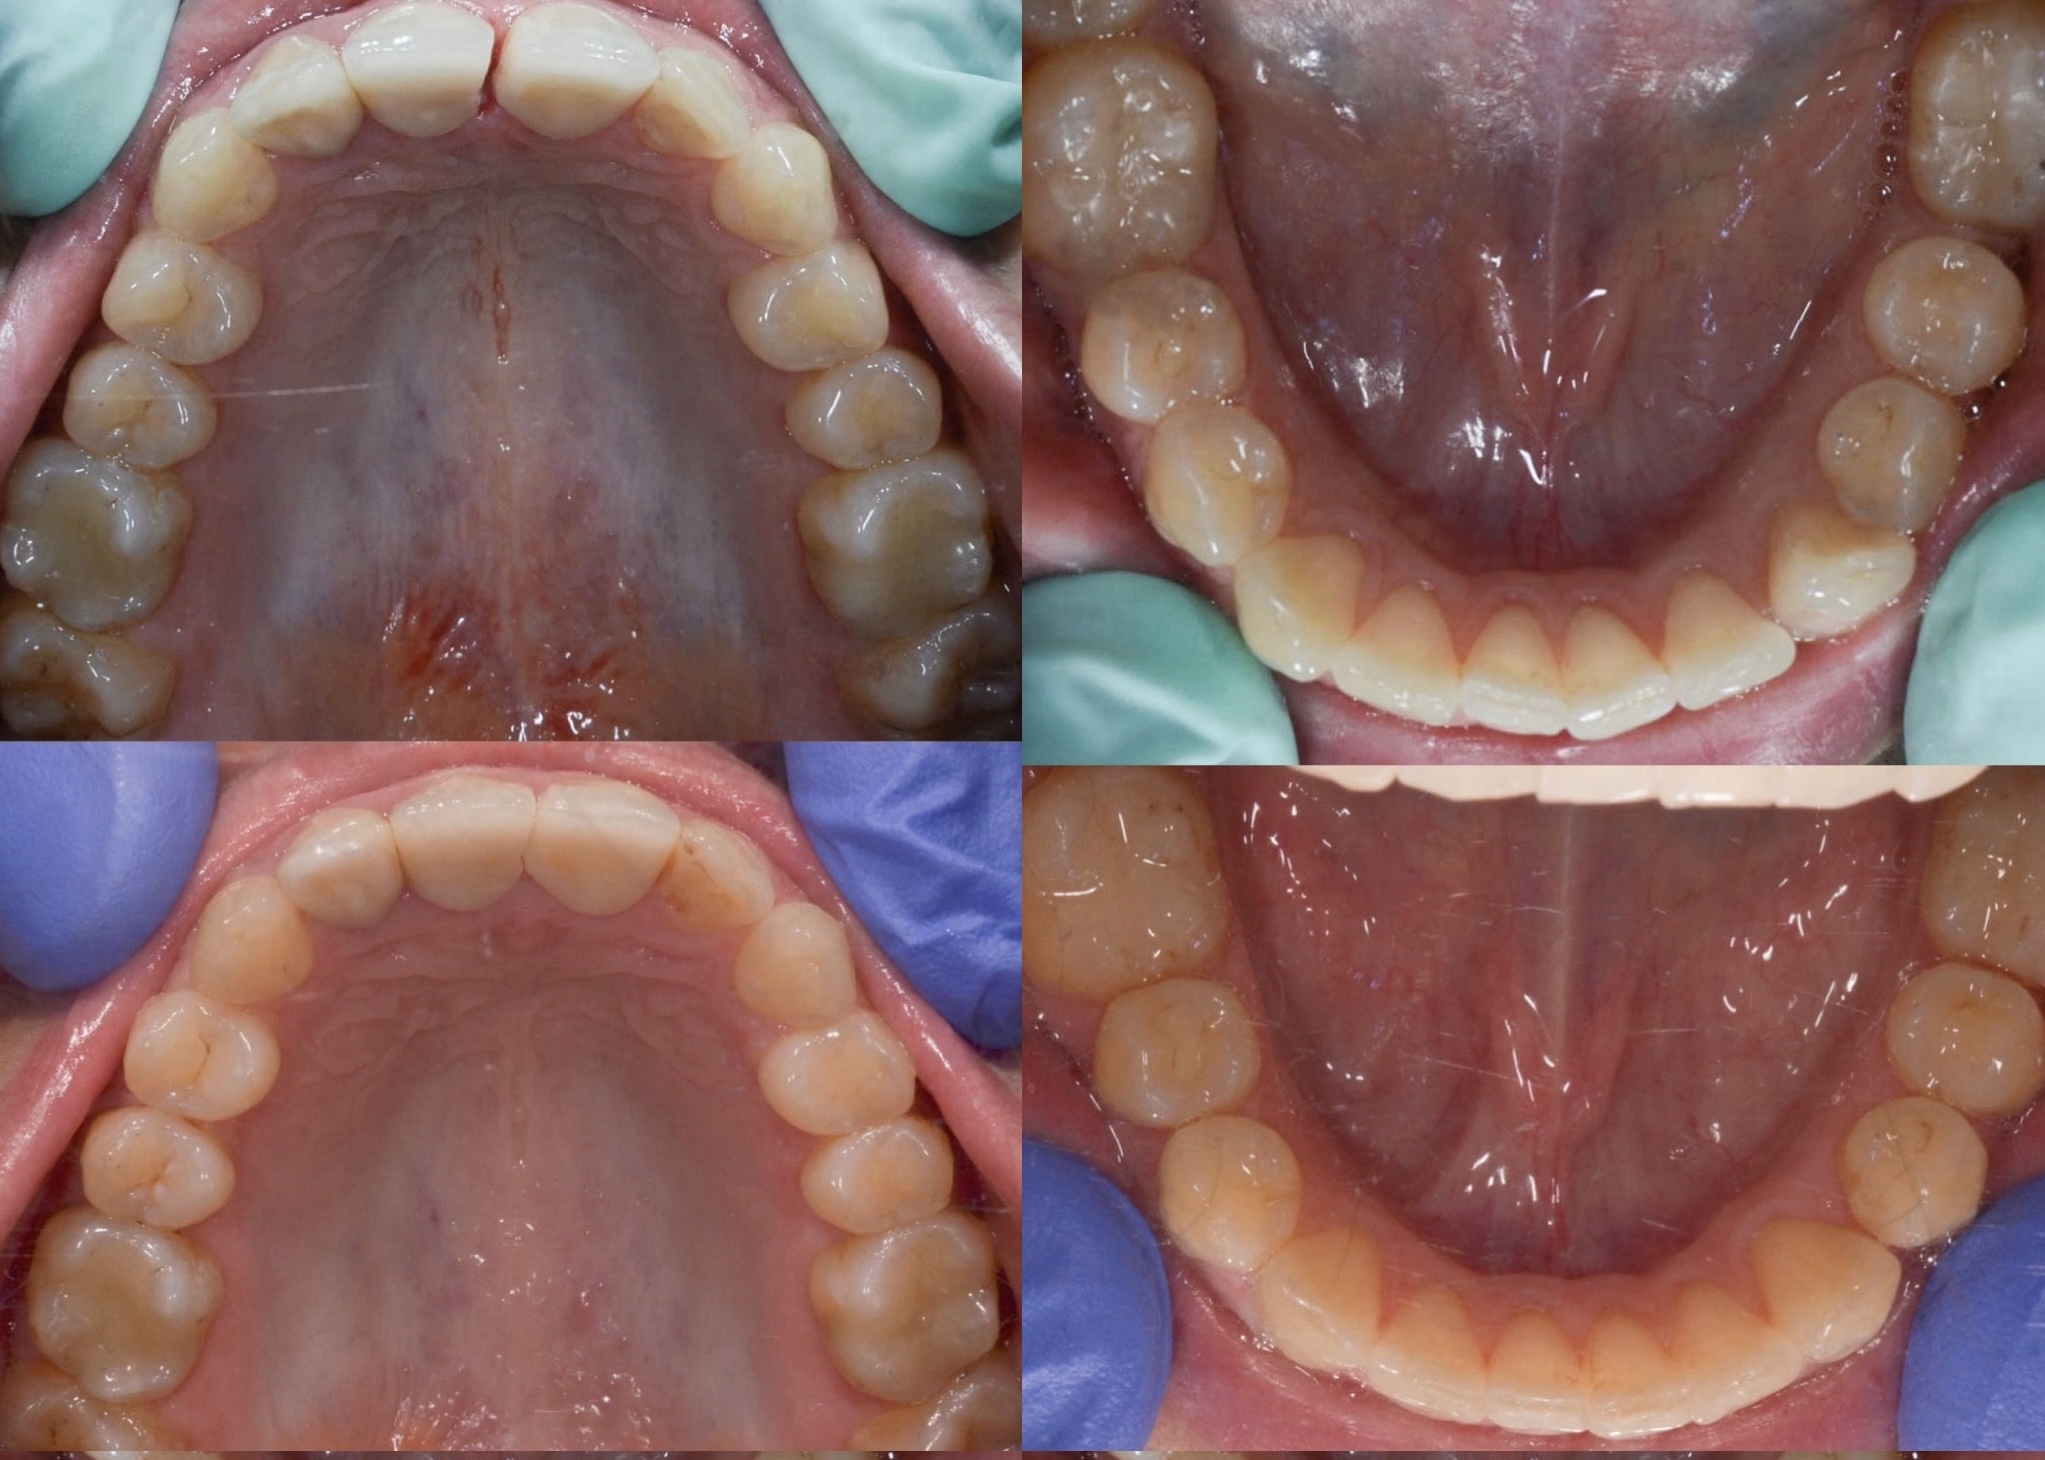

Slučaj 1: ispravljanje otvorenog zagriza i kompresije Invisalign full terapijom

Slučaj 2: ispravljanje kompresije Invisalign full terapijom- u ovom slučaju je izvađen jedan donji sjekutić

Slučaj 3: ispravljanje kompresije Invisalign full terapijom

Slučaj 4: ispravljanje kompresije Invisalign full terapijom

Slučaj 5: ispravljanje kompresije i križnog zagriza Invisalign full terapijom

Slučaj 6: ispravljanje kompresije i dubokog zagriza Invisalign full terapijom

Slučaj 7: ortodontska predprotetska terapija Invisalign full